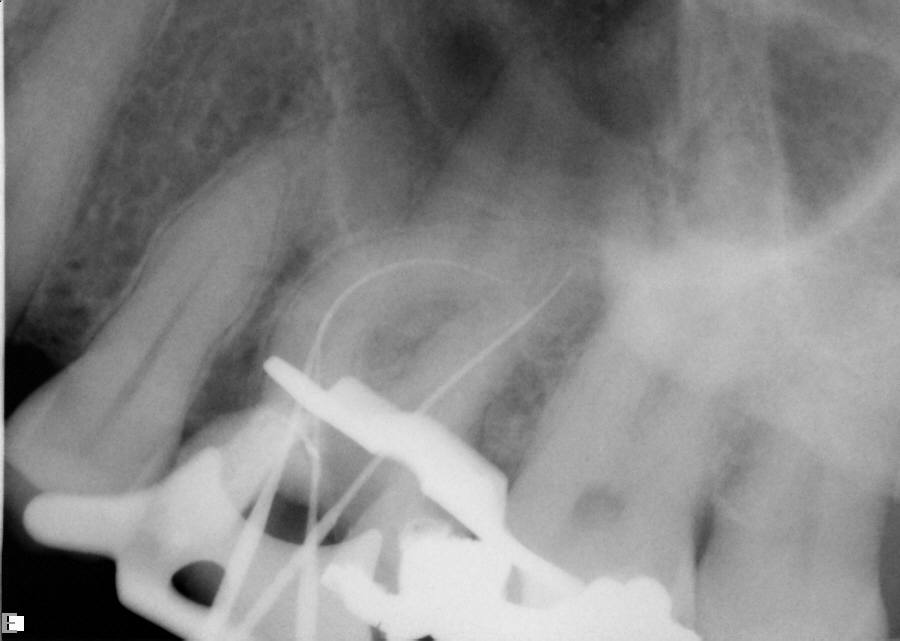

Excellent diagnosis essentially begins with two fundamental components: a doctor willing to listen to the patient’s chief complaint, and proper diagnostic tools. Among the most important tools are a precise periapical radiograph (PA) and bitewing (BW). Although a PA is often enough to provide an accurate portrayal of the patient’s condition, sometimes it alone does not suffice. Figure 1, Figure 2, and Figure 3 demonstrate a case that illustrates this point clearly. Despite two acceptable PAs (Figure 1 and Figure 2), it is difficult to assess the source of the patient’s pain to temperature. However, the BW radiograph Figure 3 provides significantly more clarity than either of the two PAs. The BW depicts localized bone loss (around tooth No. 2), a pulp stone (No. 2), a flat occlusion, numerous calcified canals, multiple restorations in tooth No. 30, and gross decay especially on tooth No. 3, which is the source of the patient’s pain to temperature. In this instance these images depict how much more useful a BW can be than just a conventional PA.

Fig 1. Foreshortened PA radiograph.

Figure 1

Fig 2. Acceptable PA radiograph.

Figure 2